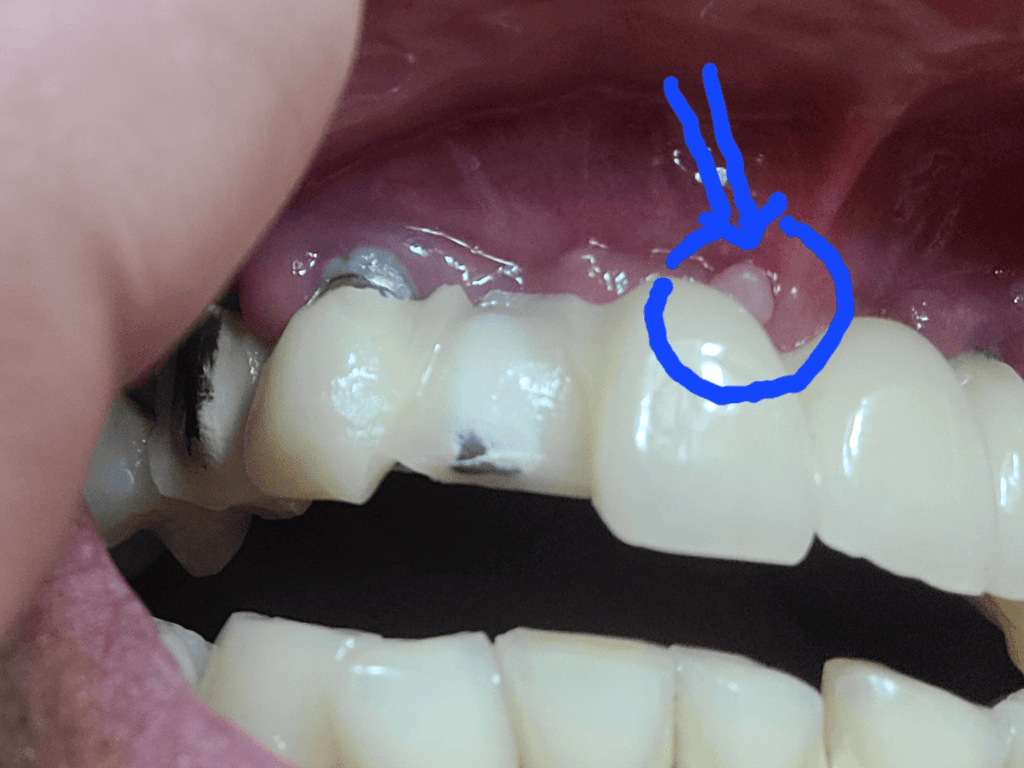

사진으로 보았을 때는 구내염인 것으로 보입니다. 구내염은 다양한 원인에 의해 나타나며 외부 자극, 스트레스 및 음식 섭취 등에 의해서도 나타날 수 있습니다. 물론 정확한 것은 치과 방문 후 검사를 해보아야겠지만 보이는 부분만 봤을 때는 구내염일 수 있어 보입니다. 해당 부위가 2주 이상 지속될때는 치과 방문 후 감별진단을 받아보셔야 합니다.

종양은 아닌거 같으며 잇몸이 증식된 것으로 보이나 보다 정확한상태한 파악을위해 빠른 시일내에 치과를 방문하여 진료를 받으시길 권장드립니다.

잇몸이 과증식되신거 같아요. 치과가셔서 사진도 찍어봐야 알겟지만, 크게 걱정할껀아니세요. 과증식이라면 그냥 마취후 제거하면됩니다.

치아뿌리쪽이 아니고 치아쪽에 가까이 생긴 고름주머니이면 잇몸염증인 경우가 많습니다.

면역력이 떨어질경우 치석이나 잇몸의 외상에 의해 고름주머니가 생길수 있습니다.

구강위생상태가 좋아지면 호전되는경우가 많습니다.

지속된다면 치과 방문해야 합니다.